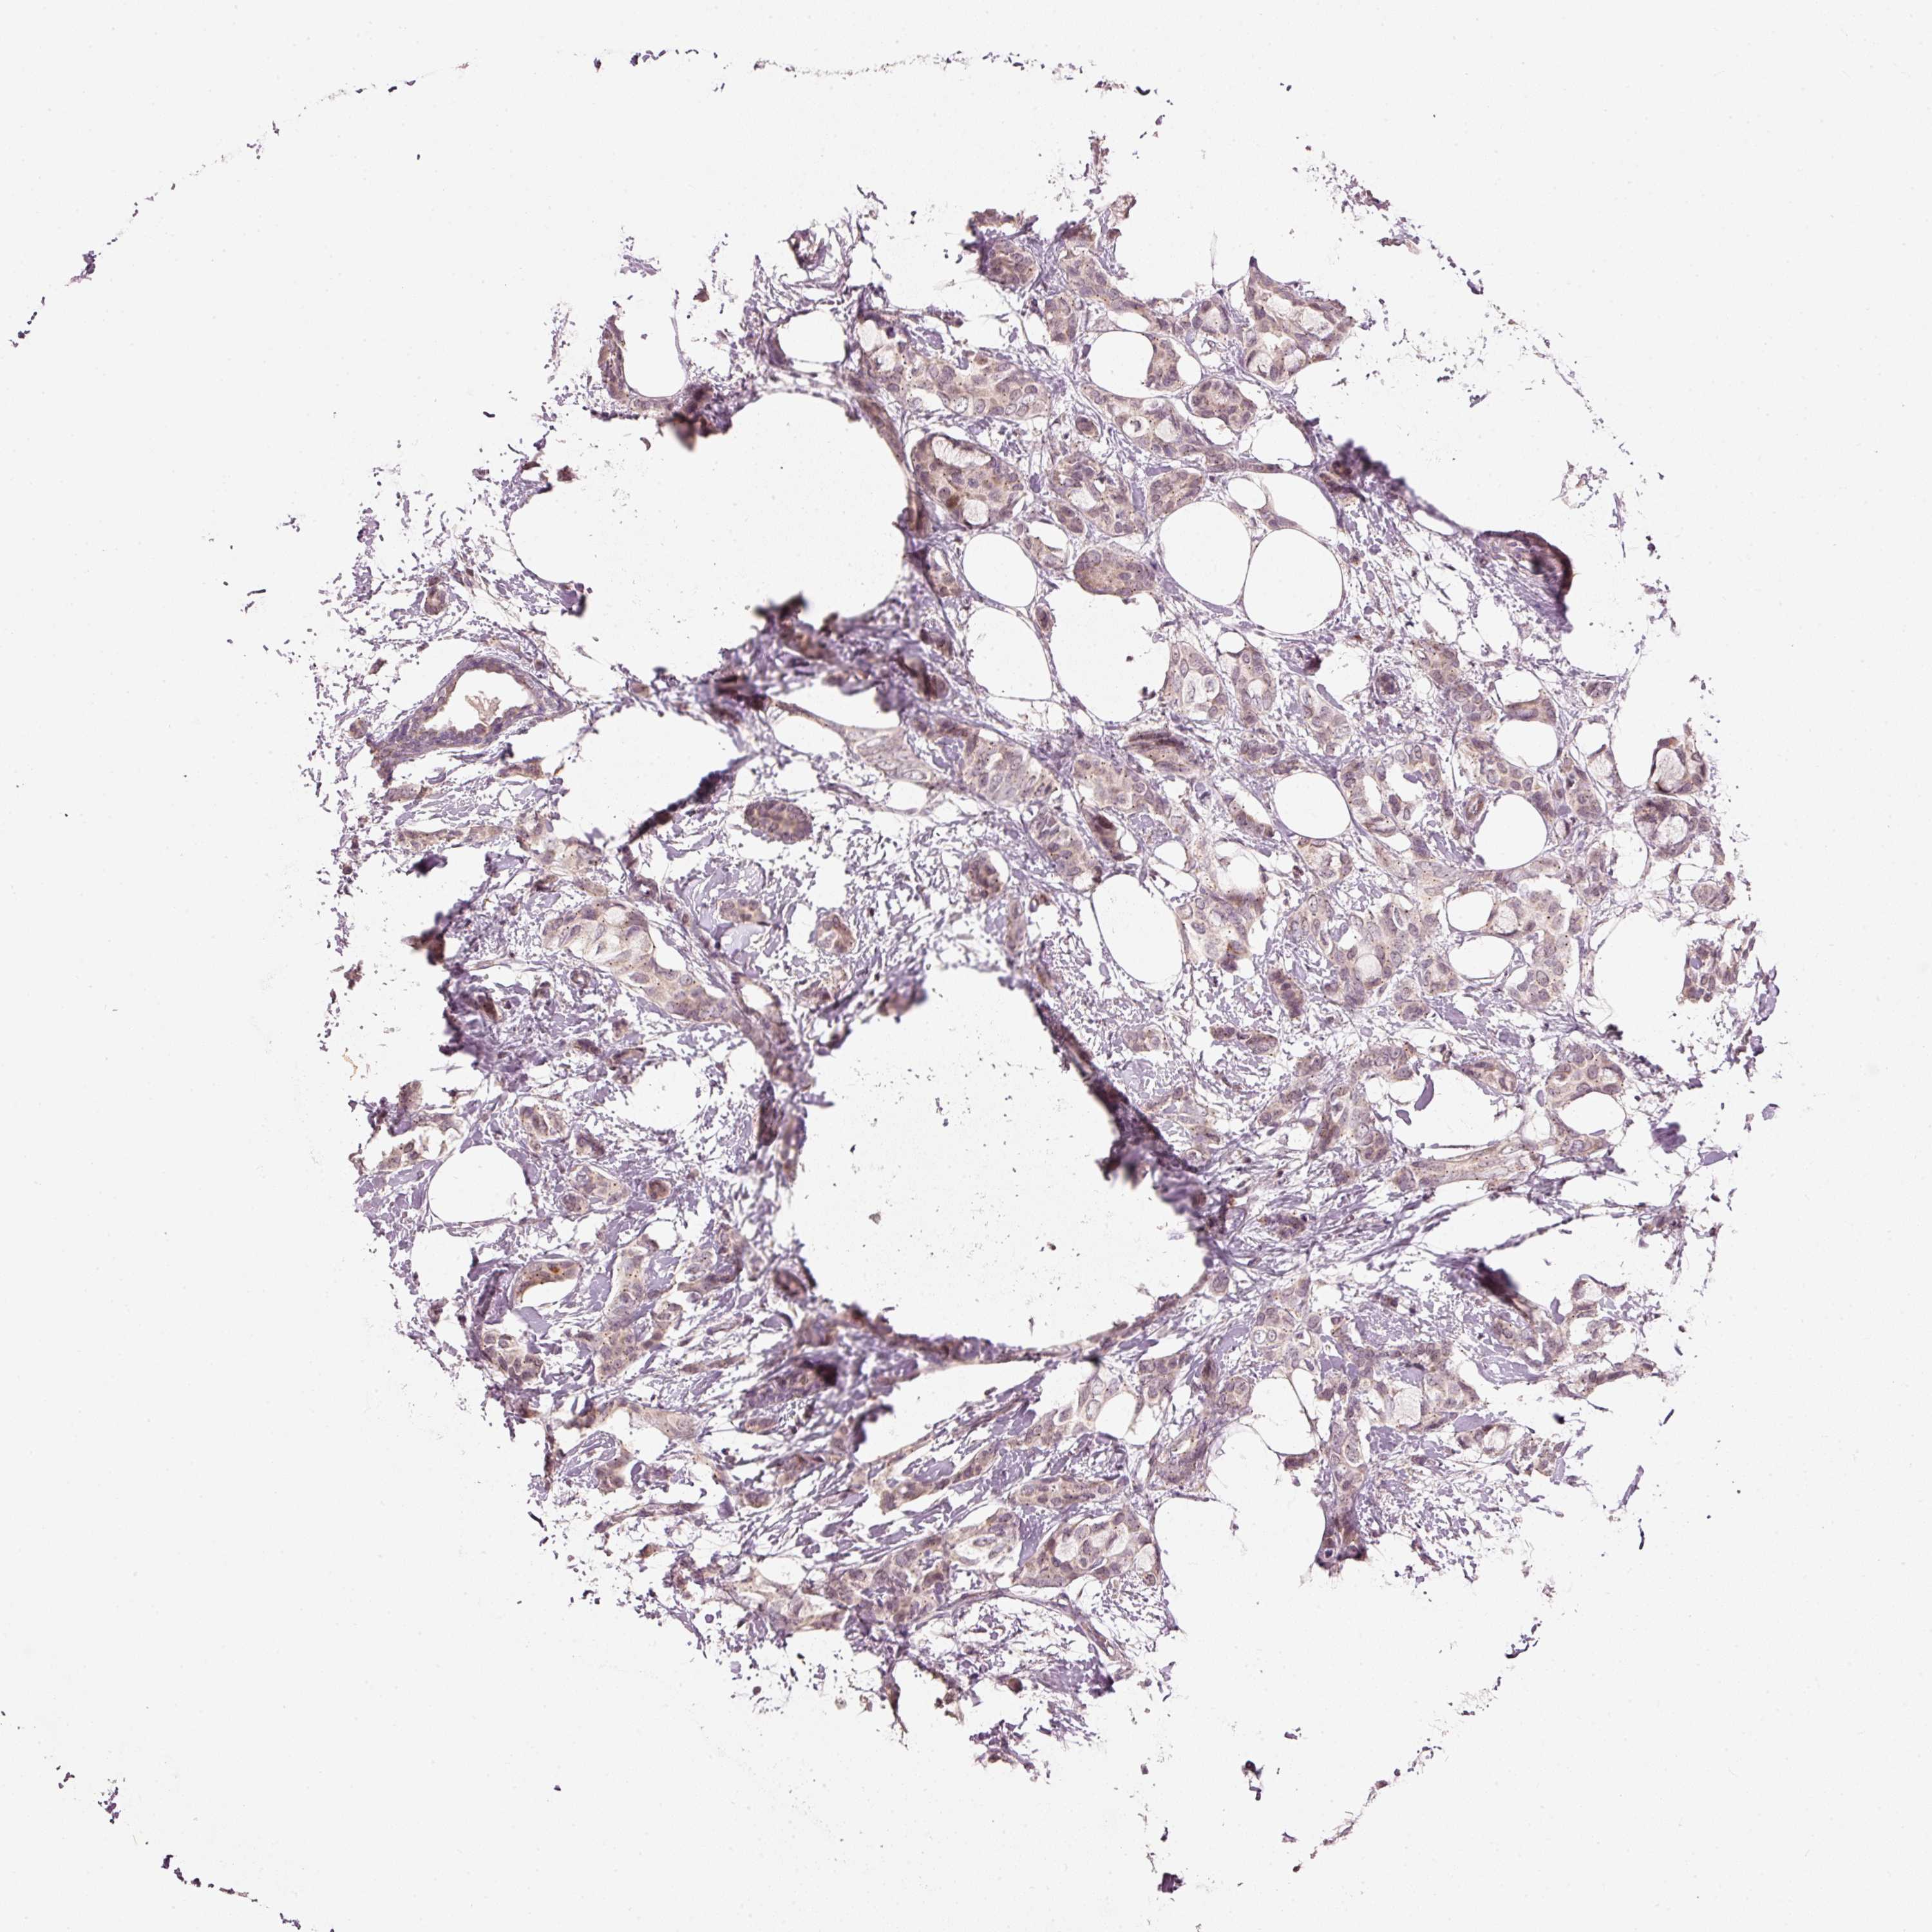

CANCER BREAST CANCER Show tissue menu

BRCA TCGA BRCA VALIDATION PROTEIN EXPRESSION